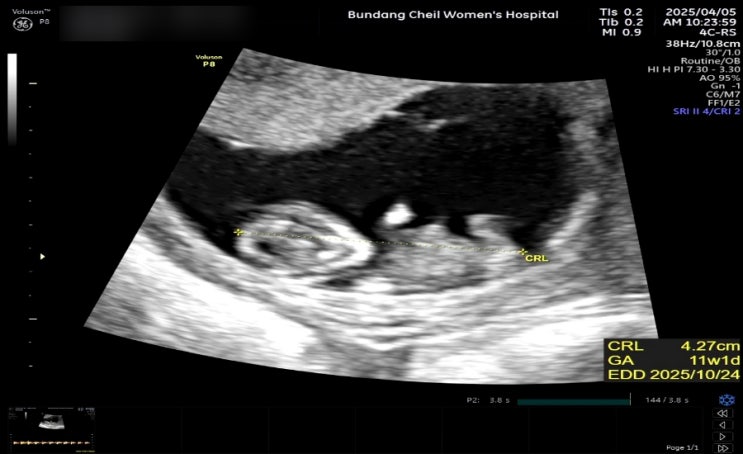

[11-12주]1차 기형아검사_정밀초음파

11주0일 점심에 신랑,어머님과 산책하고 돈까스먹고 집에와서 쉬다가 저녁에 장어탕을 끓였는데.. 격한 냄...